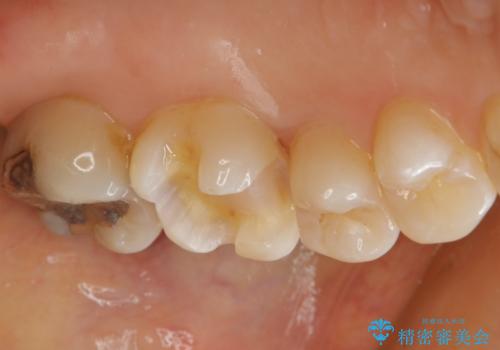

- 左上6番の銀歯をセラミックにしたいと希望され来院された患者様です。

切削量を考慮し、セラミックインレーを選択しました。

銀歯を除去したところ虫歯が深かったので、CRを詰めた上で形態を整えています。